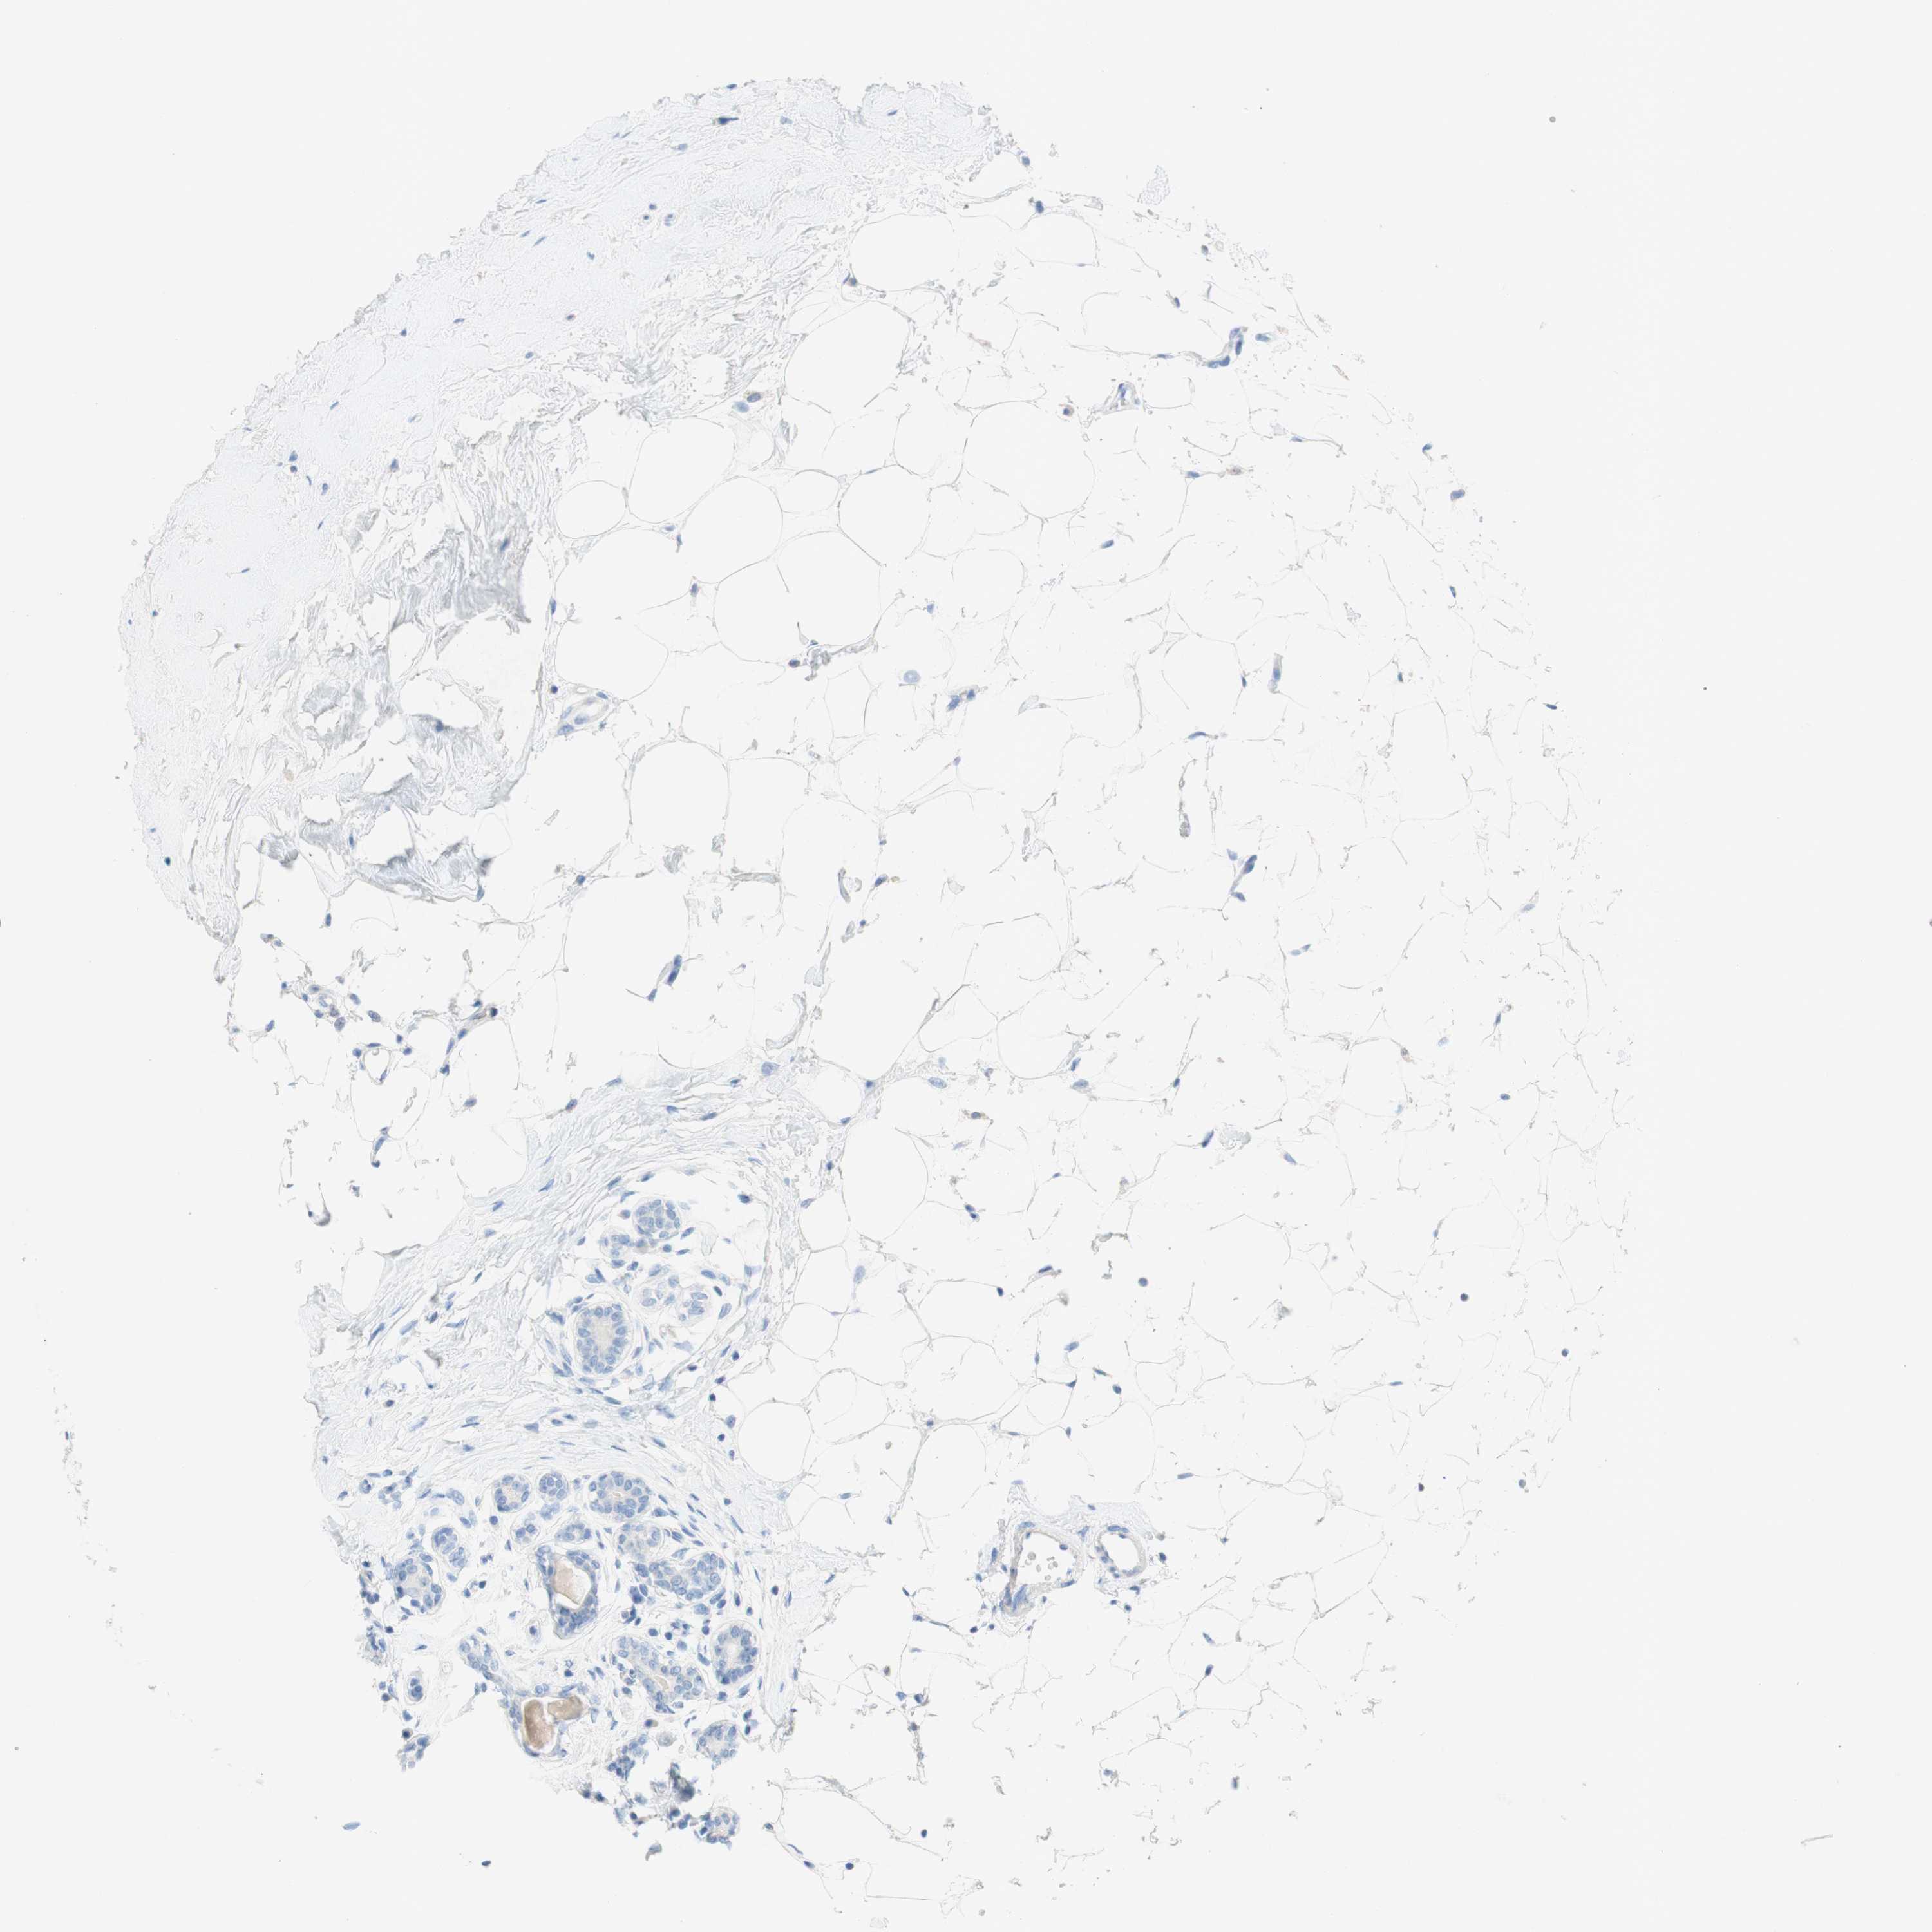

CANCER BREAST CANCER Show tissue menu

BRCA TCGA BRCA VALIDATION PROTEIN EXPRESSION